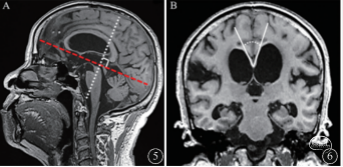

3. 胼胝体角(CA)(图5~6):CA是垂直于AC-PC连线经过PC的冠状面上形成的侧脑室内壁夹角。目前多采用CA<90°为异常,也是iNPH较特异的影像学特征。研究发现,CA<90°作为界限值区分iNPH和AD的敏感性为97%,特异性为88%,阳性预测值为93%。有研究认为,CA可用于预测分流手术的有效性。

图5~6:CA角:经PC(白色虚线)垂直于AC-PC连线(红色虚线)的冠状面侧脑室内壁夹角(白色实线间角度)(实测CA:37°)